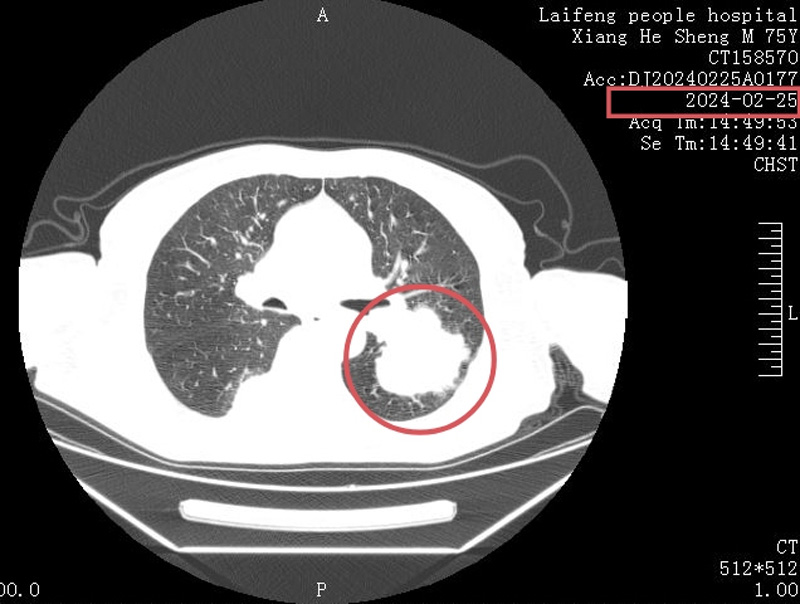

黎小兵博士在详细了解患者病情后,带领肿瘤科医护团队为向先生制订了个性化治疗方案,在经过4个周期的精心治疗后,向老先生肺部的肿瘤明显缩小,病情也得到了明显改善,对生活又充满了希望,全家人也都为此感到开心。为了表示感谢,特地向我院肿瘤科赠送锦旗。

治疗前